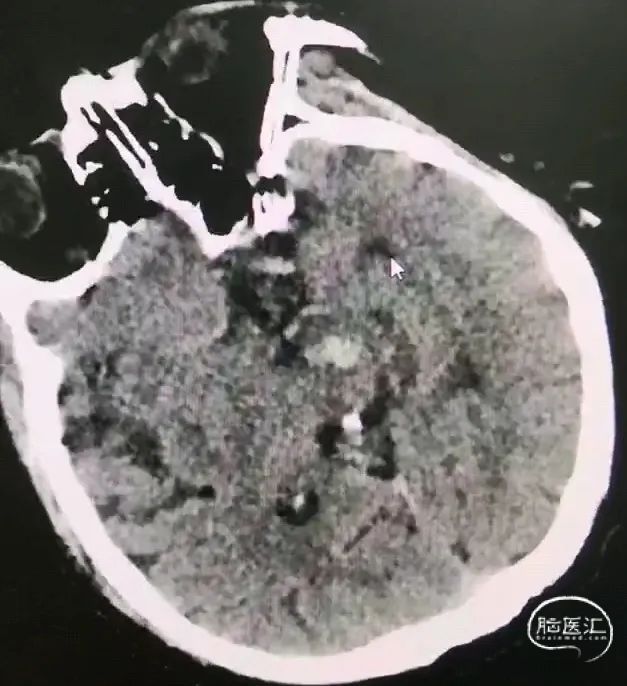

对血肿层面较少、面积较大,主要位于桥脑中下部的血肿,选择幕下经小脑半球-小脑中脚-桥脑入路;

CT扫描后测算脑干血肿穿刺靶点及路径

一口双孔,平行植入脑室引流管,测算脑室引流管植入靶点

双靶点

引流管准确到达靶点

术后尿激酶应用,术后3天复查CT,血肿引流满意